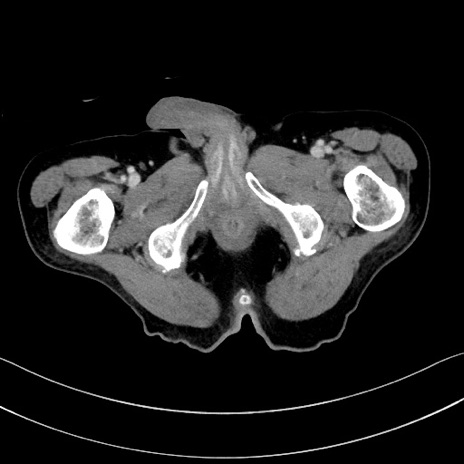

冠状断像

【症例】60歳代男性

【主訴】嘔吐

【現病歴】胃癌にて胃全摘後。食思不振が悪化し、夜中に嘔吐することがある。

【既往歴】胃癌、胃全摘、脾摘、胆摘後

【データ】WBC 5900、CRP 10.56